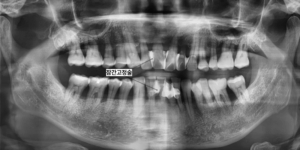

곧바로 발치하는 대신 치주소파술과

스케일링을 반복해 염증을 줄이고

상하악 전치부에는 잠간고정술을 시행하여

흔들림을 최소화했습니다.